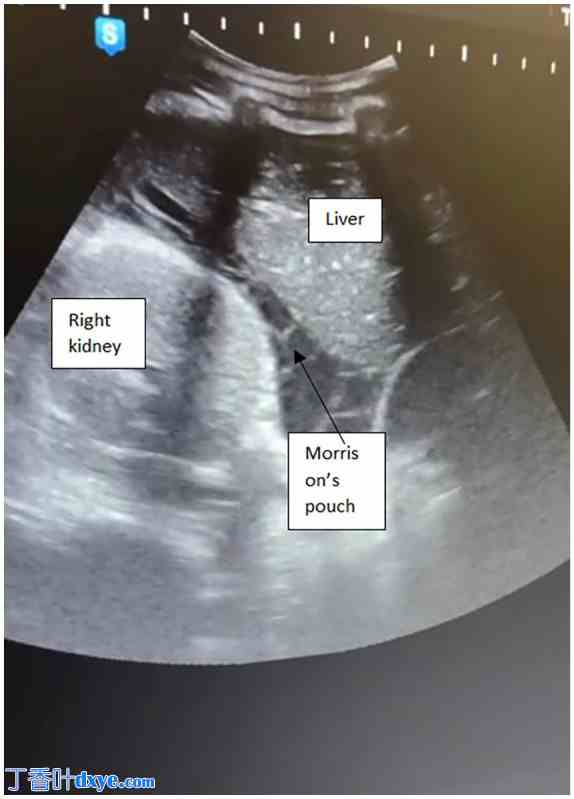

体格检查显示患者神志清醒,配合医生,定向力良好,面色苍白,卫生习惯不良。患者无发热,但心动过速。腹部柔软,膨隆,弥漫性压痛。阴道点滴出血。床边超声检查发现胎儿无法存活,但找不到胎盘。盆腔检查发现宫颈闭合。随后,作者的母婴医学专家将她转诊至正式的超声检查。超声检查证实了妊娠 25 周无法存活。然而,她的妊娠并非宫内。子宫看起来是空的。胎儿和胎盘均位于子宫后部,羊水不足(图 1)。还观察到大量腹腔积液到达 Morrison 袋,并解释为腹腔积血(图 2)。紧急安排了剖腹手术。检查显示白细胞增多(WBC 计数 = 18 × 109/L)、C 反应蛋白升高(CRP = 300 mg/dl)以及妊娠中期妇女的正常血红蛋白水平(Hb = 11.1 g/dl)。

图 2.

经腹超声检查。莫里森袋充满大量腹腔积液和小提琴样粘连,提示Fitz-Hugh-Curtis综合征。